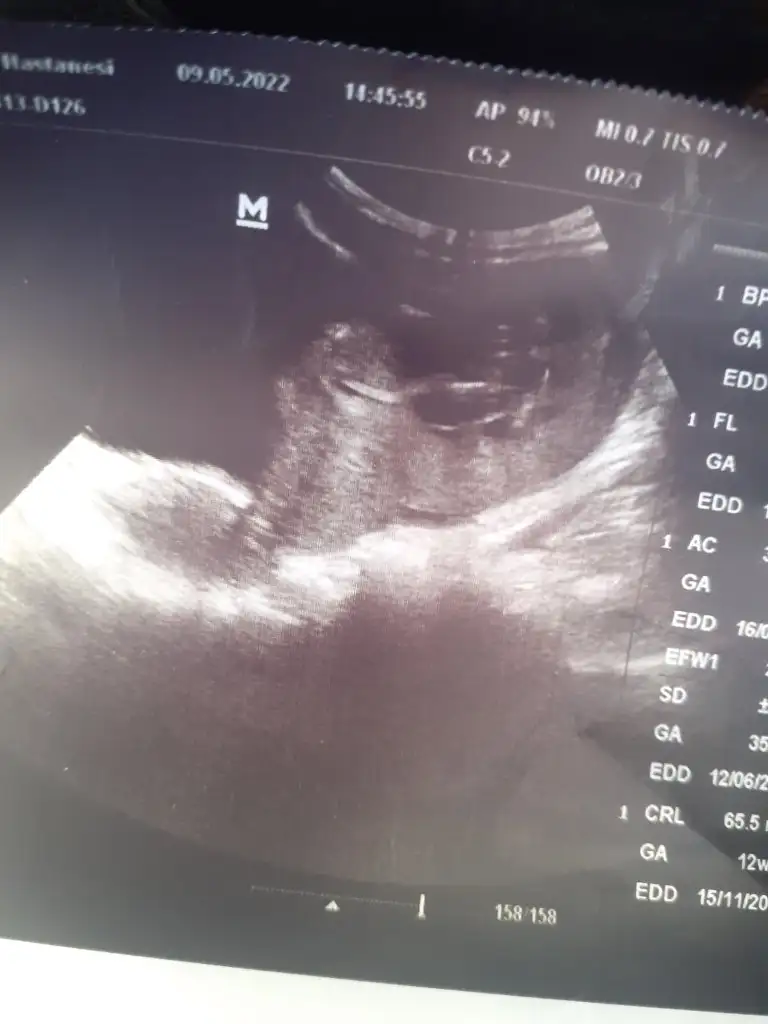

Bakarmisin